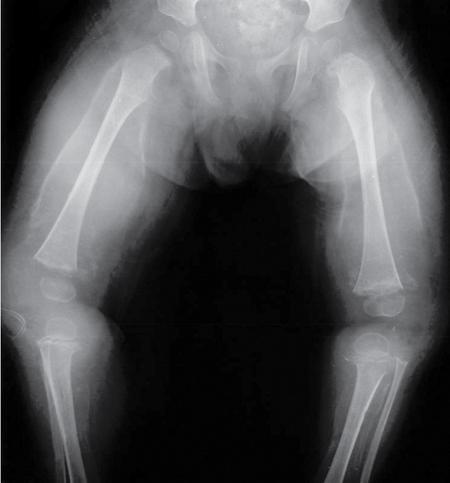

MISCELLANEOUS PAEDIATRIC RADIOGRAPHY – TECHNIQUES AND INTERPRETATION: SKELETAL SURVEY Padma V. Badhe The skeletal survey, generally performed in children, is a set of radiographs done in order to evaluate the entire skeleton. A skeletal survey, commonly used to evaluate skeletal dysplasias, acquired metabolic disorders and suspected child abuse, is still the key radiological investigation for the same. Hence, an explicit understanding of the technique along with the common disorders forms the basis of making a diagnosis in these paediatric pathologies. A skeletal survey is done for various skeletal dysplasias, non-accidental injury (battered baby syndrome) and suspected child abuse. It can also be done in cases of metabolic bone diseases, disseminated infections, multiple myeloma, eosinophilic granuloma. It is also used in evaluation of metastatic bone diseases and polyarticular arthropathy. Orthogonal views of the skull, spine, pelvis and one extremity are taken, preferable in standing position. For preterm babies/newborns, AP and lateral views of babygram may be taken. Projections: For skeletal dysplasias: Additional views: Both extremities may be taken if epiphyseal abnormalities and limb asymmetry is present. Focused views for specific pathologies may be taken. When a diagnosis remains uncertain, 1 year follow up is usually recommended. For preterm babies/newborns: AP and lateral views of babygram may be taken with additional specific views for extremities. For suspected non-accidental injury (NAI): AP and oblique view of chest is taken for better evaluation of the ribs. AP view of abdomen with pelvis. Both upper and lower limbs are evaluated. In lower limbs, two projections in AP and lateral (one with both femur including hip and knee joints; and another for foot and ankle) is taken. AP and lateral views of whole spine, skull. Oblique view of hands. A babygram should be avoided in cases of NAI, as subtle fractures are easily missed. Proper legal documentation while taking the views is very important and ideally two health care professionals must be present. For metabolic disorders: entire skeletal survey is usually not required. Specific views of hands, knees and spine may be taken with additional views depending on the suspected pathology. Centring point: Varies according to the part being examined. Angulation, collimation and orientation: Varies according to the part being examined. Images must be well collimated to obtain lower radiation dose. Detector size: Varies according to the part being examined: 8″ × 10″, 10″ × 12″, 11″ × 14″. Exposure: Ideally high kVp images are taken to reduce radiation dose. But in suspected NAI, low kVp/high mA images are recommended to better demonstrate findings. SID (Source Image Distance):100 cm Grid: Grids are not routinely used to image spine, pelvis, skull and abdomen in children. Radiation dosage: 0.3–3 mSv Essential image characteristics: Adequate spatial resolution, high signal to noise ratio, low kVp (50–70) for high contrast should be done. Excellent bone and soft tissue details are required. The presentation of skeletal dysplasia can range anywhere from minimal stunting of growth and bowing of limbs to severe dwarfism and multiple fractures. Knowledge of the commonly encountered dysplasias with an approach to arrive at a diagnosis is vital in any Radiologist’s practice The following flow chart summarizes the classification of important skeletal dysplasia: The following table summarizes the various dysplasias affecting the axial skeleton: TABLE 7.5.1.1 The following flow chart summarizes the working approach to skeletal dysplasias: Osteopetrosis (Albers-Schonberg disease/Marble bone disease) (Fig 7.5.1.1): Osteopetrosis clinically presents with anaemia/thrombocytopenia or cranial nerve compression. Radiological features include generalized increase in bone density with loss of medullary space. However, cortico-medullary appreciation with cortical thinning is also rarely seen. Bone within bone appearance with Erlenmeyer flask deformity is also noted. Pyknodysostosis (Figs. 7.5.1.2 and 7.5.1.3): patient presents with short stature. Unlike osteopetrosis, there is no anaemia. Radiographs show generalized increase in bone density with preserved medullary canal. There is mandibular hypoplasia with obtuse angle. Acro-osteolysis is also a feature. Dental caries with osteomyelitis of the jaw may be seen. Sclerosing dysplasia presenting as wavy undulating new bone formation. Usually monomelic, lower limb and along one side. The classic appearance is described as Dripping candle Wax sign. It is a Sclerosing dysplasia with radiological features of symmetric juxta-articular involvement in epimetaphyseal region. They are 1–10 mm in diameter and uniform in size. No metabolic activity is seen on bone scans. This skeletal dysplasia shows diffuse decrease in bone density with paper-thin cortex. Fractures heal in normal time but shows callus with poorly cellular matrix. Wormian bones and enlarged sinuses may be seen. Codfish vertebra (Biconcave vertebra) may be seen. Metaphyseal corner fractures are not seen in osteogenesis imperfecta that helps to differentiate it from battered baby syndrome. There are four types of OI out of which type one is most common (Figs. 7.5.1.6 and 7.5.1.7). The radiological features of MPS include Osteopenia and Universal platyspondyly. The intervertebral disc spaces are maintained. Proximal pointed metacarpals is an important radiological finding. Hurler’s syndrome show anteroinferior beaking with short and wide metacarpals. Varus deformity of humerus is characteristically seen in Hurler’s syndrome (Fig. 7.5.1.8). Mental retardation & corneal clouding is seen in Hurler’s syndrome whereas these Hunter’s disease has normal intelligence with no corneal clouding. Morquio’s syndrome shows central beaking (Fig 7.5.1.9). This skeletal dysplasia shows normal bone density with rhizomelic limb shortening and normal trunk. Narrowing of spinal canal is classically seen with decrease in the Interpedicular distance caudally. Other radiological features include trident hand (separation of middle & third fingers), Champagne glass pelvis (short, flat ilia and small sciatic notch), bullet nose vertebra and overexpansion of skull with narrow foramen magnum (Fig. 7.5.1.10). This skeletal dysplasia is characterized by normal bone density with dwarfism and normal craniofacial skeleton. The interpedicular distance is normal. There is severe platyspondyly with anterior tonguing (disappears at older age). Other radiological features include increased disc space, short stubby metacarpals, small irregular epiphysis and widened metaphysis. Anterior tonguing is a feature of Pseudoachondroplasia. This form of skeletal dysplasia involves the spine and epiphyses (Fig. 7.5.1.11). There is normal bone density with rhizomelia. Spine and Pelvis can be involved. Premature osteoarthritis can be seen. The other characteristic features include Platyspondyly and small irregular epiphysis. There are two forms Spondyloepiphyseal dysplasia Congenital and Spondyloepiphyseal dysplasia Tarda. Spondyloepiphyseal dysplasia Congenita is Autosomal dominant and shows pear-shaped vertebrae. Spondyloepiphyseal dysplasia Tarda is X Linked recessive with heaped up vertebrae. It has two forms. The first form is Conradi Hunermann syndrome which is autosomal dominant characterized by asymmetric limb shortening with metaphyseal flaring (Fig. 7.5.1.12). The Autosomal recessive form is Fatal in first few years. Rickets: Rickets refers to deficient mineralization of the growth plate in the paediatric population due to deficiency of vitamin D. In an immature skeleton, there is abnormal mineralization at the zone of provisional calcification in the metaphysis due to osteoid deposition resulting in widening of the growth plate. The features of rickets include fraying, splaying and cupping (Fig. 7.5.1.13). Fraying denotes indistinct margins of the metaphysis whereas splaying denotes widening of metaphyseal ends. Term ‘Cupping’ is used for increased concavity of the metaphysis. These findings are typically seen involving areas of active growth (e.g. distal femur and proximal tibia in the knee) Bowing is a result of associated osteomalacia leading to weakening of weight-bearing lower limb bones. Other bone deformities such as genu valga, genu varum, protrusio acetabuli can also be seen. The lower ribs may also be drawn inwards inferiorly by the attachment of the diaphragm this is called Harrison’s sulcus. Scurvy: Scurvy is a result of dietary deficiency of Vitamin C (ascorbic acid). The classic presentation is that of a patient with an increased bleeding tendency and osteopenia with poor wound healing. Features of scurvy include generalized osteopenia with cortical thinning termed as ‘pencil-point’ cortex. Other radiological findings include the periosteal reaction due to subperiosteal haemorrhage. Expansion of the costochondral junctions occurs forming scorbutic rosary. Bleeding into the joint spaces may result in hemarthrosis. Circular, opaque radiologic shadow surrounding epiphyseal centres of ossification may result from bleeding (Wimberger ring sign) (Fig. 7.5.1.14). Frankel line may be seen. It represents dense zone of provisional calcification. Lucent metaphyseal band is seen underlying Frankel line called as Trümmerfeld zone. Metaphyseal spurs may be seen that result in cupping of the metaphysis (Pelkin spur). Pelkin fracture (metaphyseal corner fracture) can also be seen. Images obtained must be of good resolution with adequate bone and soft tissue details. Additional views: They have already been described in positioning. CT Brain in can be done in cases of NAI to look for subdural hematomas. A skeletal survey is the first-line imaging modality for evaluation of skeletal dysplasia, nonaccidental injury and metabolic bone diseases. The skeletal survey must be tailored according to the respective indication. It helps to characterize syndromic patterns in skeletal dysplasias, with evaluation of complications. In cases of diagnostic dilemmas, additional focused view and occasionally yearly follow-up is recommended. A high index of suspicion is needed in utilizing skeletal survey as a diagnostic modality in NAI. At the same time, one must also remember the legal and social implications of making this diagnosis. BABYGRAM Babygram is a colloquial term used for a radiograph of the whole body of a newborn or just the chest and abdomen (thoracoabdominal babygram) on a single image. As the name suggests it is a rather non-targeted study. It is most commonly requested after line placement. Evaluation of skeletal abnormalities in a deceased foetus is typically performed using anteroposterior and lateral views of a babygram. It helps in pointing out skeletal causes of death in stillborn or dead foetuses. This will help the treating physician and parents understand the reason for baby’s death. This will also help in future genetic counselling of the couple. Sometimes chest or abdominal radiographs of the baby are requested but due to radiographers error or inexperience with small babies, there is inclusion of the region not to be assessed leading to a false babygram. Babygram is most frequently done after line placement in neonates, to view the position of the umbilical vein or artery catheter and to confirm appropriate placement. It is a useful modality in skeletal dysplasias (Fig. 7.5.1.15) like osteogenesis imperfecta, thanatophoric dysplasia and chondrodysplasia punctata. It can also be used for skeletal deformations probably caused by foetus akinesia and in cases of Caudal regression syndrome. In stillborn foetuses, it is used for evaluation of skeletal dysplasias prior to an autopsy (Fig. 7.5.1.16). It is also used in screening for surfactant deficiency and in cases of Necrotizing Enterocolitis in preterm babies where it can help to see the bowel dilatation, intramural and portal venous gas. It can be done in aneuploidies like trisomy 18 and in cases of sudden infantile death syndrome. All the essential equipment and room need to be prepared including the exposure factor. This should be done prior to placing the baby on the table to prevent any neonatal heat loss. Ensure that the baby is correctly identified. Give brief explanation to the patient’s parents regarding the procedure, its risks and benefits. Ensure that the accompanying relative is not pregnant (if female). Parents/guardians/nurses should be instructed to hold the baby with arms above the head and legs straight down. Sandbags/tapes can be used to immobilize the baby. Avoid taking the radiograph when baby is crying. Normal appearance: The endotracheal tube should lie in the lower third of trachea, distance can vary with position of baby’s head. Umbilical artery catheter has an inferior dip along the internal iliac artery, which then turns superiorly along the aorta. The tip should lie in the mid-thoracic aorta (T6–T10) or lower (L3–L4) away from aortic branches to prevent any thrombosis. Umbilical venous catheter does not have the inferior curvature, but rather a posterolateral angulation to the right near the liver through the ductus venosus. The tip should lie in the superior IVC or right atrium at T8/T9 vertebral level (Fig. 7.5.1.17). Portal venous gas may be seen initially after insertion. In a stillborn foetus, the approximate gestation age of the foetus and corresponding ossification centres must be known. In early gestation, the lack of appearance of an ossification centre may be mistaken for skeletal dysplasia. Both chest and abdomen should be included. In a rotated patient, the distance between the spinous process to medial end of clavicles will be asymmetric. The medial end of clavicle should overlap the lung apex, if above, suggests lordotic image. Motion artefacts to be reduced as much as possible. A crying neonate may result in an expiratory film, and hence must be evaluated accordingly. In evaluation of skeletal dysplasias in the newborn, additional views of skull and hand have to be obtained. Baby gram is a useful diagnostic investigation for position of the paediatric umbilical catheters. It helps in general survey in skeletal dysplasia (Fig. 7.5.1.18). It is a simple, effective study in deceased foetus for diagnosis and further counselling, sometimes obviating the need for an autopsy. As baby gram is a non-targeted study, it increases the dose of radiation for the baby. As the exposure settings remain same for the entire body of the baby, the quality of the image decreases. This increases the chances of missing subtle findings. The babygram in a neonate is currently used to localize umbilical catheters. In stillborn fetuses, it is still an important study for documenting and confirming skeletal dysplasias. Understanding the normal appearance as per gestation age and patterns of various common skeletal dysplasias is essential for evaluation. Being a non-targeted study, it should not be used as an alternative study to evaluate the chest or abdomen considering radiation exposure and poorer image quality. INVERTOGRAM Invertogram was first described by Wangensteen and Rice in 1930. It was used as a first investigation to be ordered in evaluation of infants with clinically diagnosed or suspected Anorectal Malformation (ARM). ARM is a serious but surgically treatable congenital malformation with approximate incidence of 1 in 5000 live births. Though the diagnosis of this condition is based on clinical history and physical examination, imaging plays an important role in deciding the type of ARM, and associated complications to aid in management. International classification of anorectal malformations is as follows. Syndromic association is seen as a part of VACTERL defects, trisomy 21 13 and 18, Klippel Feil syndrome, cat eye syndrome etc. The main indication of Invertogram is to evaluate anorectal malformation in a neonate. A radio-opaque marker is placed over the external anal opening. Infant is held inverted by holding both thighs, maintaining this posture for at least 5 minutes before taking an X-ray in true lateral position (Fig. 7.5.1.19). Exposure is made during inspiration. The Invertogram should ideally be done 24 hours after birth as, the rectal gas may not reach the terminal segment if study is done too early. Pubo-coccygeal line (PCL) is drawn from upper border of pubic symphysis (which corresponds to centre of pubic bone on lateral X-ray) to sacrococcygeal junction. I point is the inferior most point of ischial ossification centre. A line which is drawn parallel to PC line passing through the I point is called I line. ‘A’ point is represented by marker placed at anal pit. The position of rectal pouch gas shadow is observed with respect to these lines and appropriate diagnosis is made (Fig. 7.5.1.21). A diagnosis of high ARM is made when gas shadow of rectal pouch is cranial to PCL. If rectal pouch gas shadow is in between PCL and I line, it is called as intermediate ARM and if it is caudal to I line, it is diagnosed as low ARM. Gas in urinary bladder or vagina or beaking of gas shadow of rectal pouch indicates fistula into one of these sites. Associated congenital abnormalities like spinal defects are also looked for in the invertogram (Fig. 7.5.1.22). Invertogram done too early (less than 24 hours) may not demonstrate rectal gas. Meconium plugging the terminal segment gives false position of the rectal gas. Positioning can cause discomfort to child and an irritated crying child actively contracts the sphincter muscles, pushing the gas shadow higher. Rectum may be pulled cephalad due to gravity in inverted position. The rectal gas may escape through an associated fistula. Erroneous interpretation can also occur due to sacral anomalies and when gas in vaginal cavity is misinterpreted as distal rectal gas. Both ischial bones should superimpose and terminal blind loop should be well distended. It is an easily available modality and can be done quickly, does not require additional equipment. It has lesser radiation dose as compared to CT invertogram. It provides a rough guide as to the type of ARM and decides management. Higher localization of obstruction due to various causes like meconium plugging, imaging done too early etc. as described above in pitfalls. It is more uncomfortable to the baby as compared to the prone cross-table lateral view, and a crying baby contracts the puborectalis leading to erroneous results. K. L. Narasimharao et al. modified the technique and proposed cross-table lateral view for evaluation of infants with ARM’s which has shown equal or better information and has now replaced invertogram (Fig. 7.5.1.23). Prone cross-table lateral view is considered equivalent or even better in determining the level of anomaly. Positioning is in this view is prone in genupectoral position (at least for 3 minutes). It is taken in true lateral and during inspiration. The lines used to delineate types of ARM is essentially the same as in an invertogram. It is preferred over invertogram as relatively easy positioning of the infant and less discomfort allows for better cooperation of neonate during the study. It also eliminates the effect of gravity. ARM with fistula is better delineated as, in an invertogram, fistula/gas is at the highest level and gas may escape through it. CT invertogram is another modality that delineates anatomy better but is rarely used. In the era of cross-section imaging, MRI and USG have opened new modalities for accurate diagnosis of ARM, but invertogram being readily available, inexpensive, quick and cost-effective is used as first investigation for evaluating a patient with suspected or confirmed case of ARM. Cross-table lateral view has replaced invertograms as it is more patient-friendly and equally effective. UPPER GASTROINTESTINAL SERIES Rushit S. Shah An upper gastrointestinal (GI) study is a radiographic examination of the GI tract from the pharynx to the ligament of Treitz after oral administration of contrast agent. The use of upper GI studies is gradually declining with the increasing availability of paediatric endoscopy and the challenge for the modern radiologist to work in conjunction with the surgeon and gastroenterologist to select the right patients for an upper GI series. However, the upper GI series remains the key for demonstrating many anatomical abnormalities. The upper GI series is also useful in evaluating gastro-oesophageal reflux in conjunction with 24 pH monitoring. The upper GI examination is useful in evaluating many conditions including but not limited to: